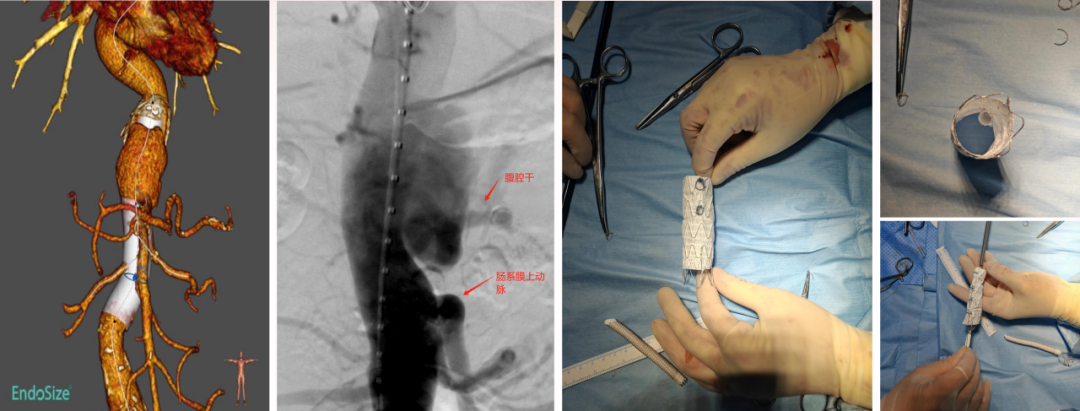

病例1 两开窗:

病例2 四开窗:

手术时间382分钟

造影剂用量320ml